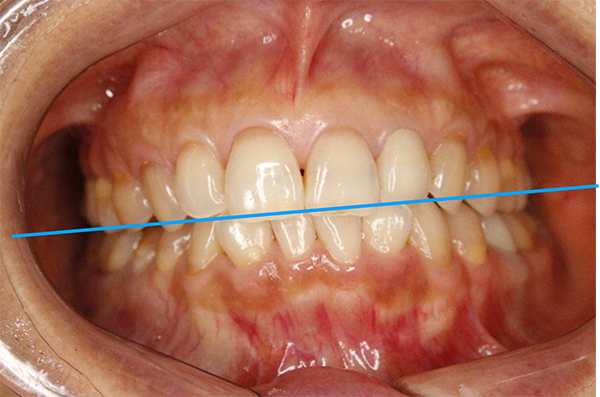

上の写真のように、治療開始前は「まっすぐ正面を見てください」と言っても、どうしても顔が曲がってしまう状態でした。また、「咬合平面」と呼ばれる上の歯並びのラインが、正面から見ると右下がりになっていました。

治療後の写真は、以下のとおりです。

噛み合っている面に傾きがなく、床に対して真っすぐになりました。また、「真っすぐ正面を見てください」と伝えたときに、首が曲がらなくなりました。3Dデータを見ても、接触点(緑色と赤色)が全体に分散しました。

患者様いわく、不均衡な筋肉の緊張が取れて、食いしばりも気にならなくなったとのこと。余計な力がかからないので、顎が疲れることもなくなったそうです。顔の傾きは顕著に改善していますね。